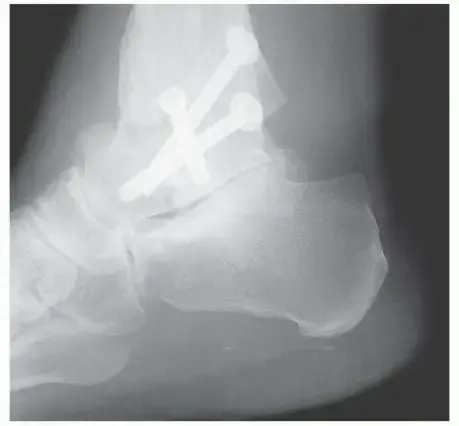

القدم والكاحل

آلام القدم المزمنة؟ اكتشف الأسباب والعلاج قبل فوات الأوان